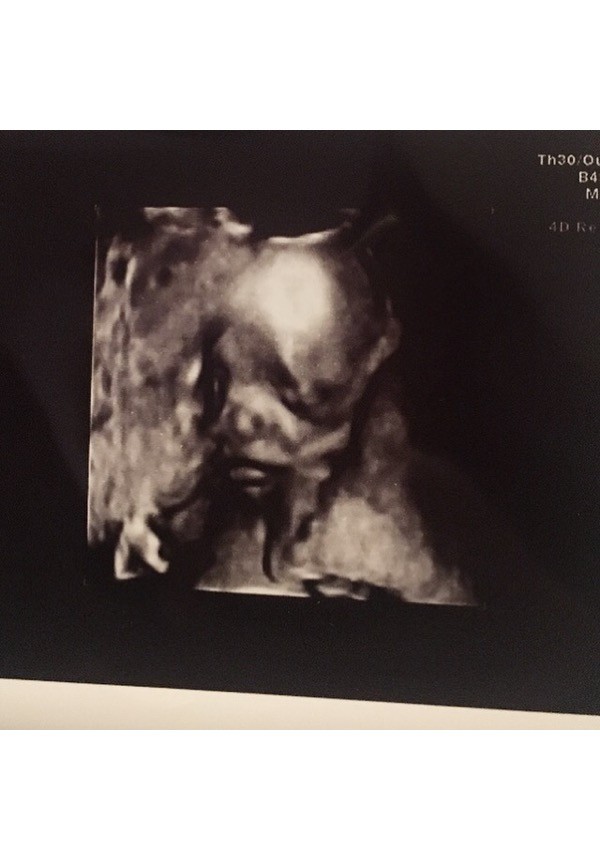

Hej dziewczyny! Wpadłam tylko na chwilę, bo muszę popisać pracę na zaliczenie na studiach. Chciałabym pochwalić się Wam, że byłam wczoraj u mojej gp. Z dzidziusiem wszystko ok, posłuchałyśmy serduszka, 140 biło

pięknie skakało i machało kończynami

Niestety pani doktor nie zmierzyło go

płci też nie podała, bo podobno za słaby sprzęt. Za 3 tygodnie połówkowe 3d, więc mam nadzieję, że już będę wiedziała, kto tam siedzi. Była ze mną mama, bo sama nie miała nigdy usg w ciąży. Strasznie się wzruszyła

Czy któraś z Was miała połówkowe 3d ?? Jakie wrażenia ?